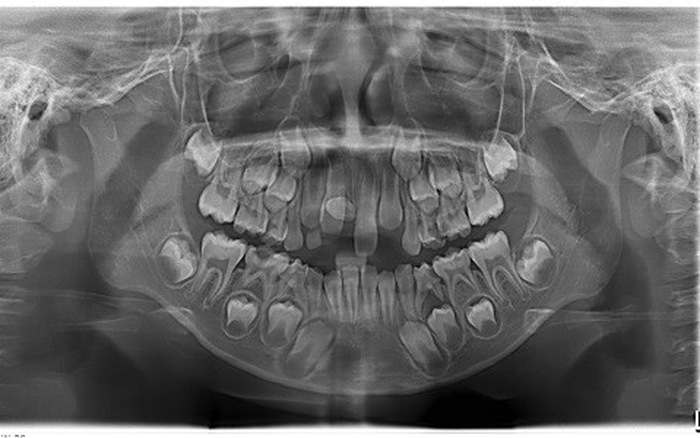

Chụp X – quang răng toàn hàm: Phim chụp X – quang toàn hàm sẽ được bác sĩ sử dụng để đánh giá tổng quan về các mối liên hệ giữa răng, xương hàm và hệ thống dây thần kinh mọc xung quanh răng. Bên cạnh đó cũng giúp bác sĩ xác định được tình trạng răng mọc ngầm dưới nướu, hoặc răng khôn mọc lệch để có phương án điều trị tốt nhất.

- Đối với trẻ em: Trẻ em cũng sẽ cần có chỉ định chụp X – quang để xác định tình trạng răng mọc lệch, sai khớp cắn cũng như sâu răng để có biện pháp điều trị tức thời, tránh lây lan sang các răng khác.